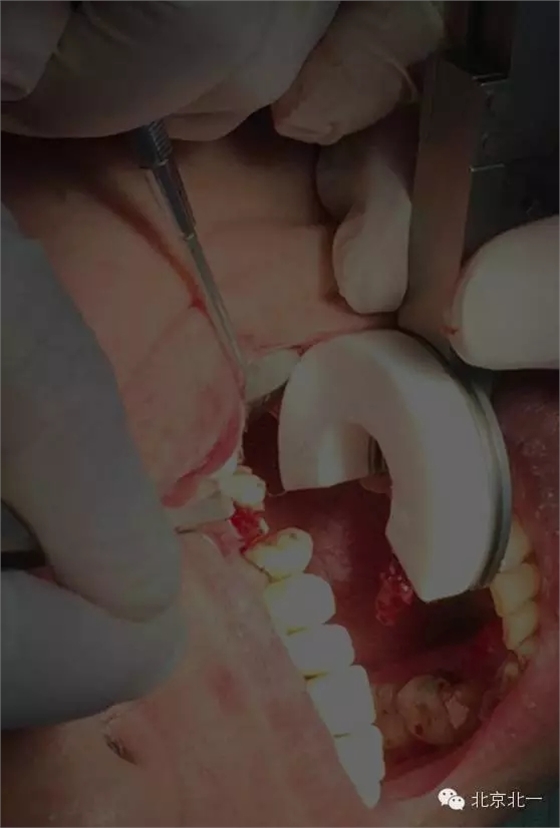

分享BENEX微創(chuàng)工具拔牙一例:

總結(jié):一、器械非常高大上,價(jià)格昂貴,能夠避免傳統(tǒng)拔牙方式最骨造成擠壓傷。此器械通過牽引的方式來拔除殘根,

二、單純用此器械可能會(huì)效果不佳,需要配合其他微創(chuàng)拔牙刀(例如雅典刀)先進(jìn)行切割牙周膜,再通過牽引把牙微創(chuàng)拔除效果更好。